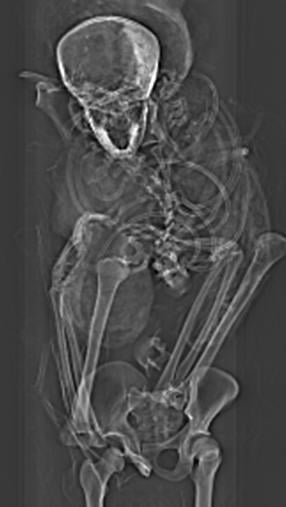

But computed tomography (CT) scans of the mummified remains of Seqenenre revealed new details about his head injuries, including previously undetected lesions that embalmers had skillfully concealed.

The authors of the new paper offer a novel interpretation of the events before and after the king's death based on the computer-processed X-ray images: Seqenenre had indeed been captured on the battlefield, but his hands had been tied behind his back, preventing him from defending against the attack.

For example, the CT scans, combined with other evidence, suggest the execution had been carried out by multiple attackers, which the scientists confirmed by studying five different Hyksos weapons that matched the king's wounds.

The CT study also determined that Seqenenre was about 40 when he died, based on the detailed morphology revealed in the images, providing the most precise estimate to date.

In addition, the CT study revealed important details about the mummification of Seqenenre's body. For instance, the embalmers used a sophisticated method to hide the king's head wounds under a layer of embalming material that functioned similarly to the fillers used in modern plastic surgery. This would imply that mummification took place in a real mummification laboratory rather than in a poorly equipped place, as previously interpreted.